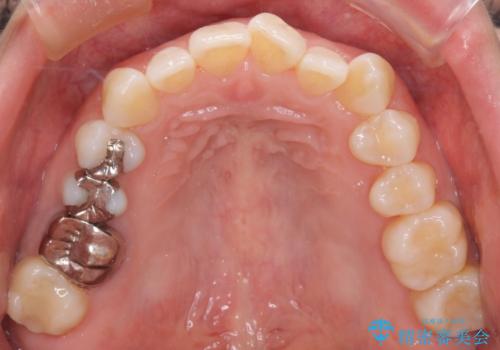

- 上下前歯のがたつきを主訴に来院されました。

口元も下げたいということもあり、上2本抜歯を行い治療を行いました。

抜歯を行い、前歯のがたつき、前歯の出ているところを改善できました。